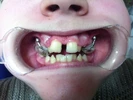

Diş Çapraşıklığı

Ayrık Dişler

Ortodontik Malokluzyonlar

Sınıf 1 Malokluzyonlar